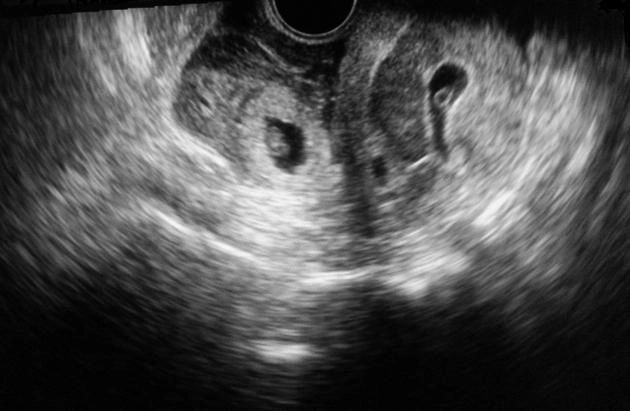

• VI. Thai ngoài tử cung

• Thai ngoài tử cung đoạn vòi (Tubal ectopic pregnancy)